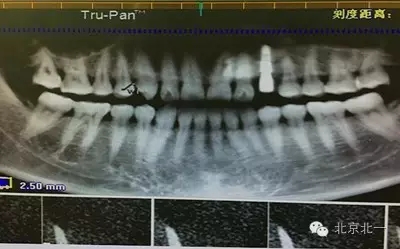

患者種植一月后種植區(qū)不適,偶有疼痛來院拍片發(fā)現(xiàn)23埋伏牙,與種植體相鄰,如圖一、二、三、四所示。